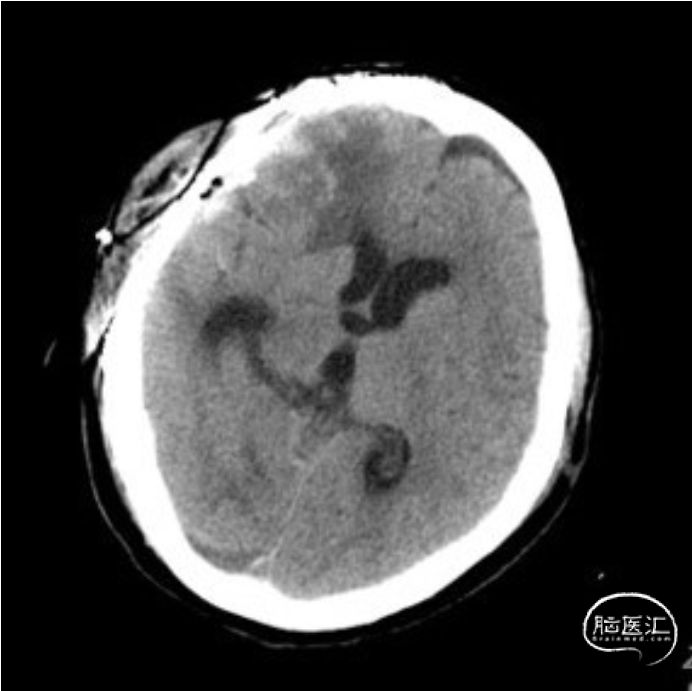

颅骨修补钛网修补术前后CT:术前术后颅内情况稳定。

颅骨修补钛网修补术后逐步拔除腰大池引流管和硬膜下引流管,拔管后患者病情稳定,意识清楚,顺利出院并转回当地医院康复治疗,术后多次复查头颅CT:颅内情况稳定,脑室稍有扩大。本例后期是否会出现脑积水,以及需要分流手术进一步干预,还有待进一步随访观察。